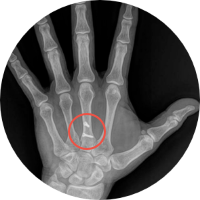

Humanos

• Niños

• Adultos

• Pacientes geriatras

• Seguimiento post cirugía ortopédica

Ideal para pacientes con incapacidad para trasladarse al hospital o moverse. Fracturados, con fijación externa, osteoporosis, niños, adultos, pacientes geriatras, seguimiento post cirugía ortopédica.